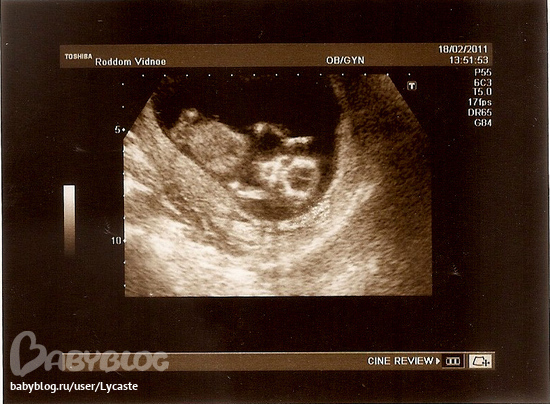

В понедельник ходила к гине, официально в декрете, выдали обменную карту. Вчера ходила на УЗИ. Масяня развивается хорошо.